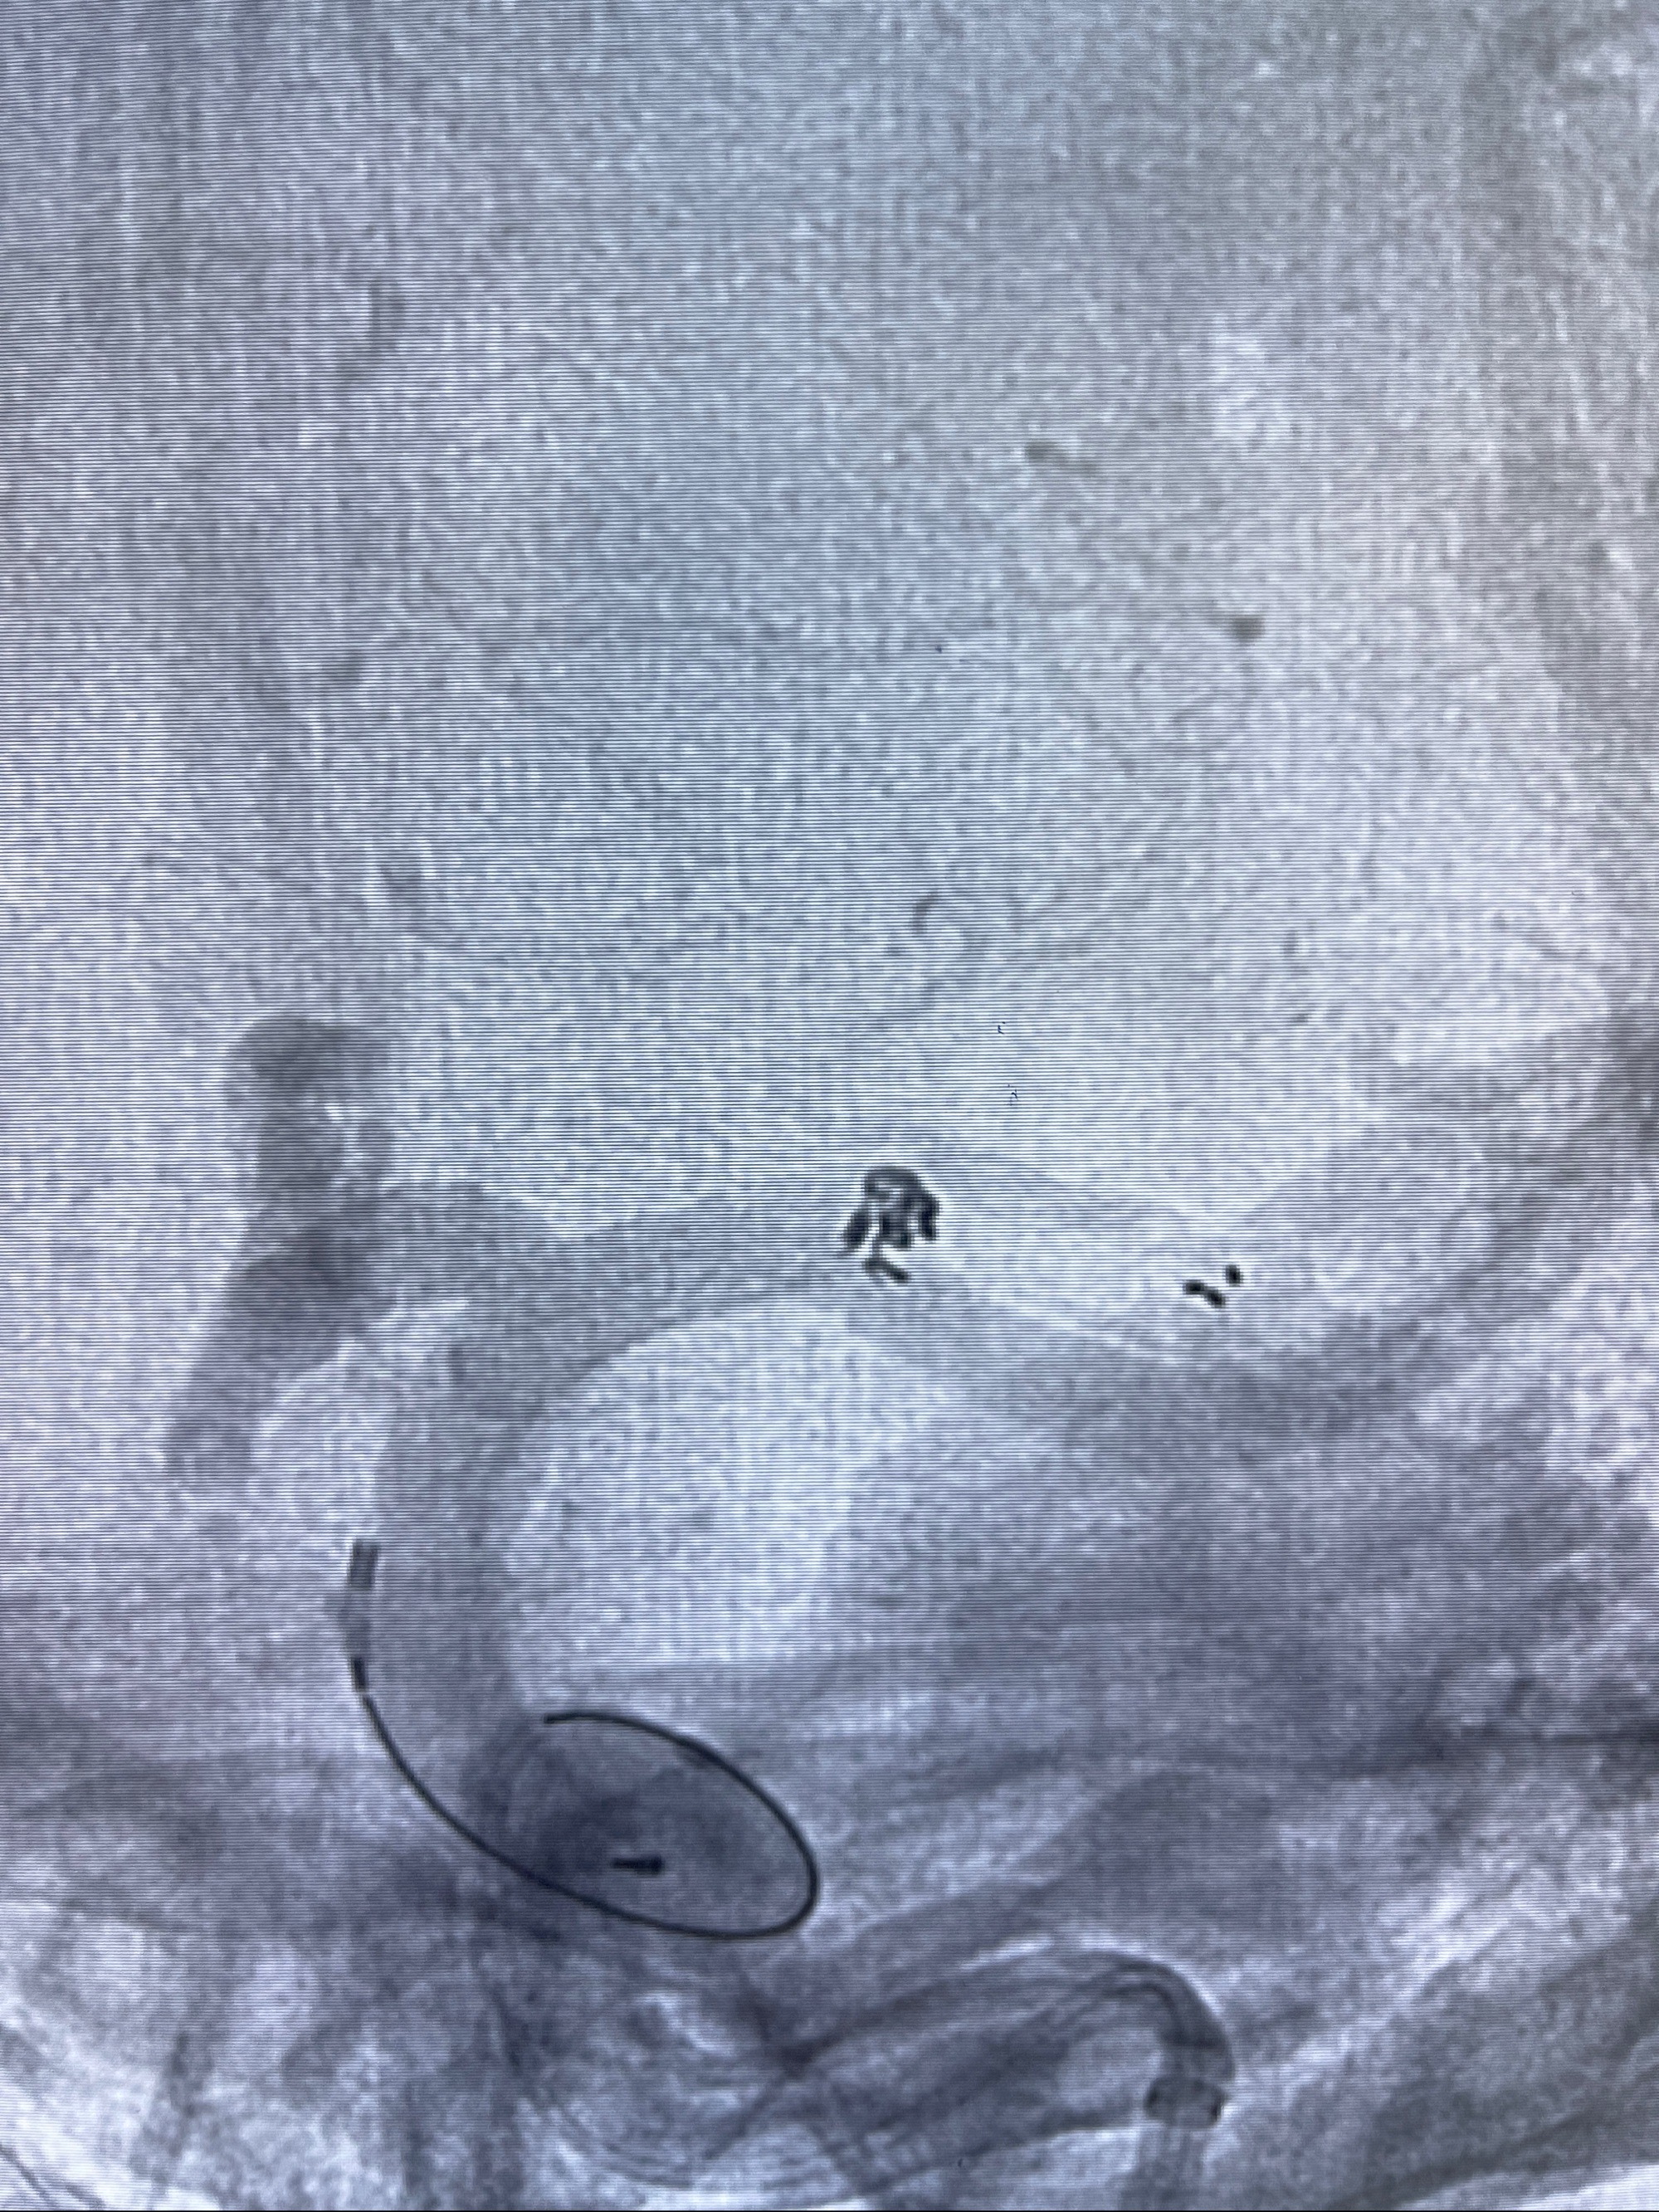

2023-08-14DSA:

左侧大脑中动脉动脉瘤,约2.6-2.8-3.4-2mm大小(瘤颈部、瘤体部、瘤高)

术后即刻CT